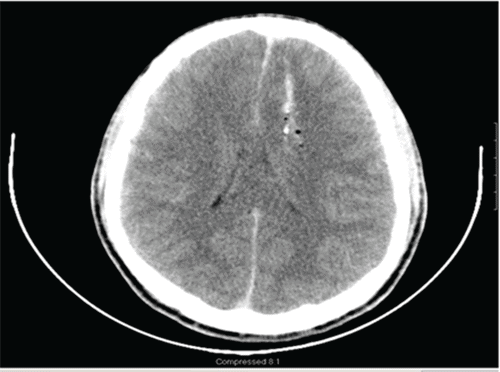

Focused assessment with sonography in trauma (FAST) revealed a diffusely hypokinetic left ventricle without tamponade or pericardial effusion. Initial chest X ray (CXR) demonstrated mild bilateral pulmonary edema (Figure 1A). CT scan of the head showed a ballistic fragment entering the left posterior parietal area, terminating in the left parasagittal anterior frontal lobe without contralateral injury (Figure 2). Imaging also revealed subarachnoid and subdural hematomas with a 3 mm midline shift.

Figure 2. Head CT (superior to inferior views). Published with Permission

Bullet trajectory through the left posterior parietal area, terminating in the left parasagittal anterior frontal lobe. No contralateral injury